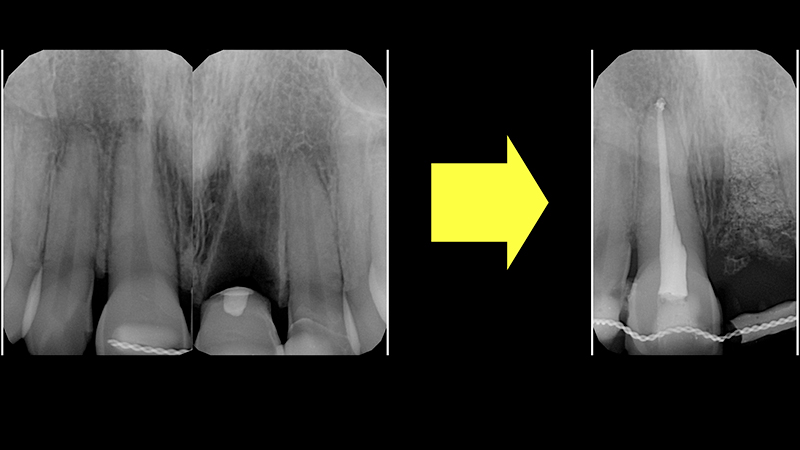

2. Rigenerazione ossea dell'alveolo 2.1 con Bio-oss e Muco-graft. In questa fase, il provvisorio fresato è stato cementato ai denti adiacenti con un filo metallico e composito. Dopo 5 mesi, ho ottenut il volume osseo necessario per poter posizionare l'impianto (Fig. 10a, Fig. 10b, Fig. 10c).

Rigenerazione ossea

Fig. 10b - Rigenerazione ossea.

CBCT dopo 5 mesi

Fig. 10c - CBCT dopo 5 mesi.

Seconda fase

L'obiettivo è inserire un impianto nella cresta ossea rigenerata e ripristinare il volume del tessuto gengivale cheratinizzato nell'area vestibolare circostante.